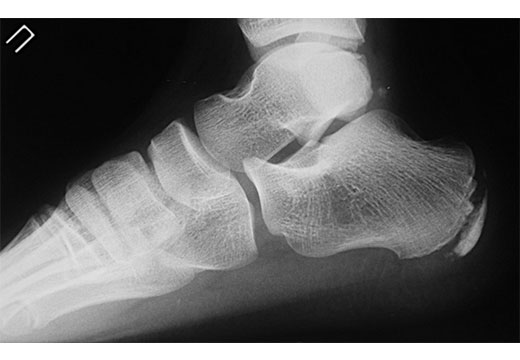

Остеофит можно спутать с многократно повторяющимися сухими мозолями на пятке. На ощупь отличия между костным, сухожильным наростом не всегда ощутимы, поэтому некоторые пациенты не торопятся к врачу за диагнозом. Помимо визуального осмотра стоп на предмет вальгусной/варусной деформации пациенту назначают рентгенографию, которая покажет, в чем причина шишки на пальце: остеофит или воспаление сухожилий – ретрокальканеальный бурсит. От диагноза зависит план лечения.

Если рентген не показал признаков костного нароста на пятке, больному назначается магнитно-резонансная томография стоп для уточнения диагноза, установления степени воспаления сухожилий, причин. Шишка на пятке сбоку – основание полагать, что у пациента не остеофит, а воспаление мягких тканей. Избавляться от натертостей на пяточках можно в домашних условиях с помощью отваров из лечебных трав, заменой обуви на комфортную.